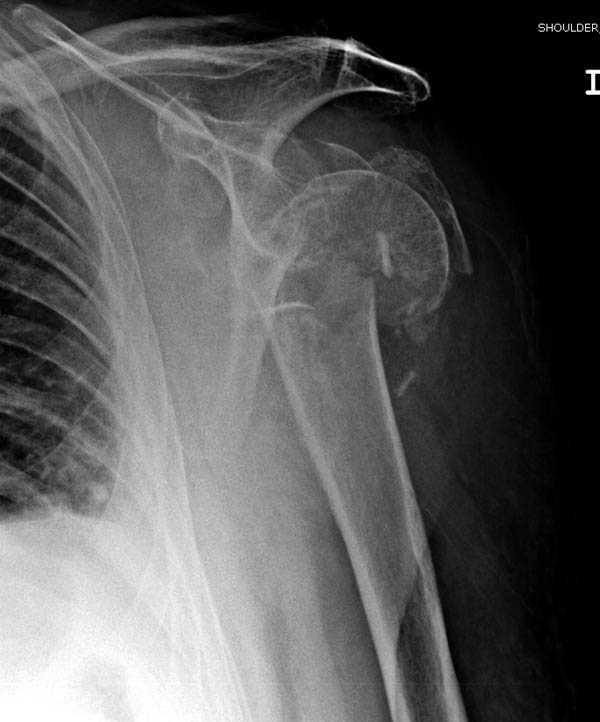

дополнительные снимки по протезированию

Имя     : Shoulder 2.jpg

Тип     : image/jpeg

Размер  : 48068 байтов

Url     : http://weborto.net:8080/pipermail/ortho/attachments/20090420/0ada04e1/attachment-0004.jpg